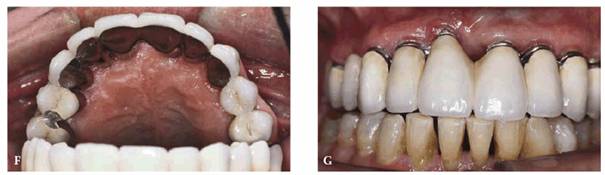

In instances where the patient has had posterior bite collapse and advanced

rehabilitation. Such a case is illustrated in Figures 23-19A, 23-19B, 23-19C, 23-19D, 23-19E, 23-19F and G, and 23-19H and I using interim bonding followed by a telescopic

fixed prosthesis.

Figure 23-19A: This 65-year-old man was embarrassed by the appearance of his front teeth.

Figure 23-19B: Using the principles previously outlined in this chapter, composite resin bonding was done to immediately improve the patient's appearance and stabilize the dentition.

Figure 23-19F and G: The superstructure was first cemented with petrolatum and zinc oxide for 1 week to help fully seat the case.

Figure 23-19H and I: Before and after treatment comparison show a greatly improved esthetic result. Note the patient's lower lip line. He felt comfortable that, because of his low lip line, none of the exposed metal margins would show.